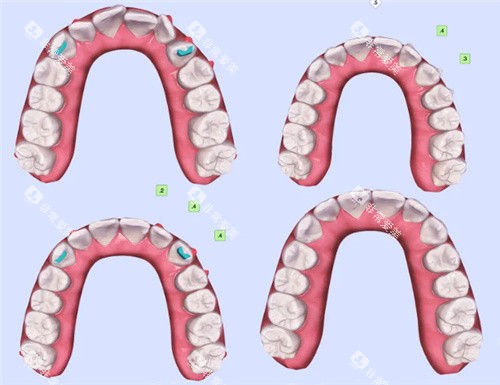

(三)隐形矫正

国产隐形矫正

价格区间:2 万 - 4 万元

进口隐形矫正

价格区间:3 万 - 6 万元

项目介绍:美观、舒适,可自行摘戴,不影响日常生活和工作,适合对美观有较高要求的患者。